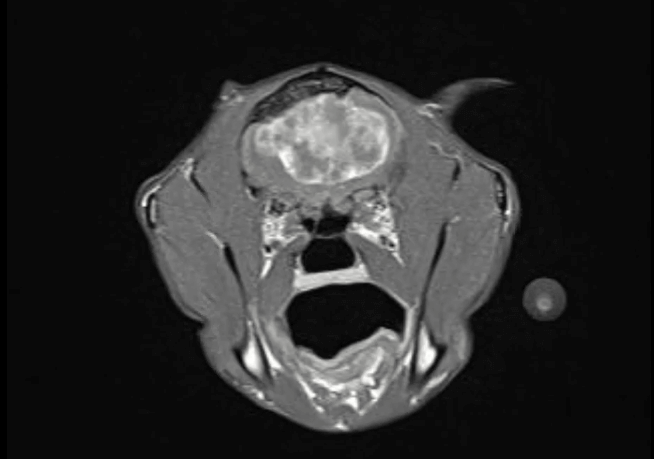

Neurochirurgie

Gehirntumore bei Hunden und Katzen sind leider gar nicht selten. Wir forschen an der chirurgischen Behandlung dieser Erkrankung.